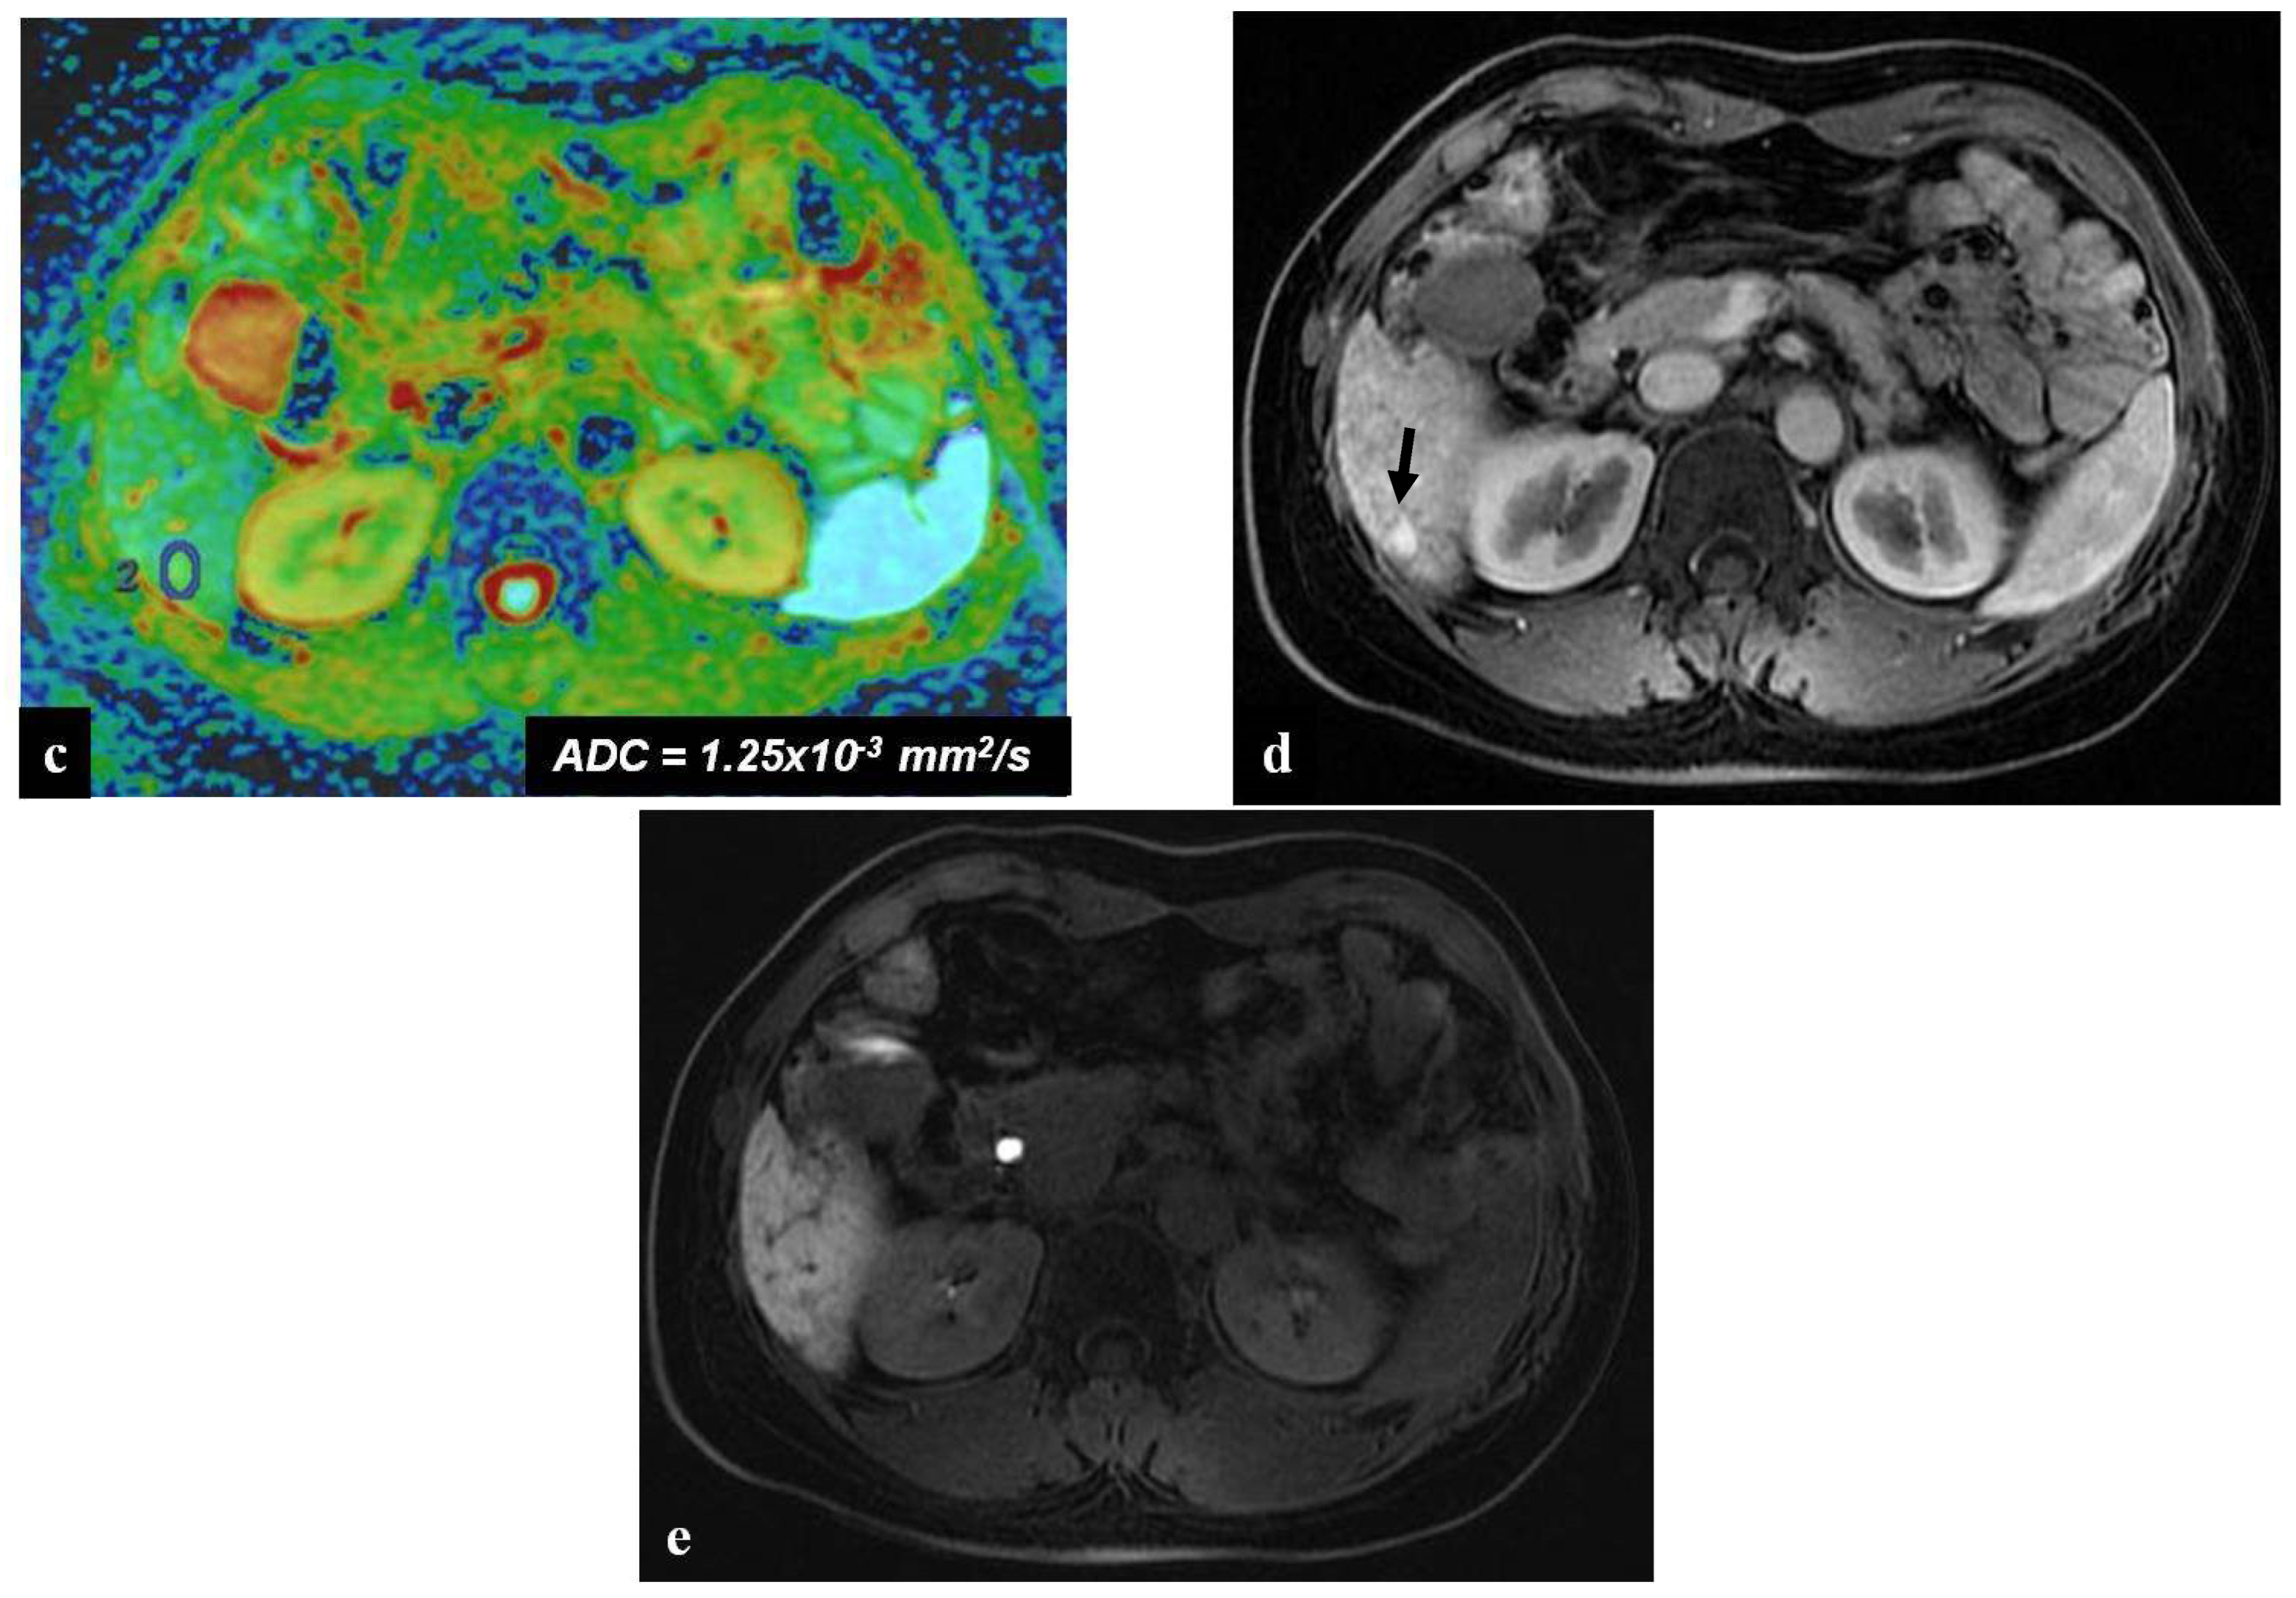

- Han, N.Y.; Park, B.J.; Sung, D.J.; Kim, M.J.; Cho, S.B.; Lee, C.H.; Jang, Y.J.; Kim, S.Y.; Kim, D.S.; Um, S.H.; et al. Chemotherapy-induced focal hepatopathy in patients with gastrointestinal malignancy: Gadoxetic acid–enhanced and diffusion-weighted MR imaging with clinical-pathologic correlation. Radiology 2014, 271, 416–425. [Google Scholar] [CrossRef]